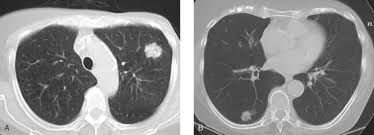

Can A Ct Scan Show Breast Cancer - Best Scans To Detect Cancer Envision Radiology : After detecting the location of the tumor, the area will be biopsied for testing in the lab.. Ct scans are inaccurate for treatment monitoring after cancer treatment, a ct scan is unable to determine whether masses leftover are cancerous: The area covered in the scanning can be determined. Bone scans, positron emission tomography (pet), and computed tomography (ct) all continue to be employed alone or in combination for the detection of breast cancers suspected to have spread. But the risk associated with these tests is worth the benefit, in most cases. A sentinel lymph node biopsy may first be performed to determine whether cancer has spread to the lymph glands under the arm.

The contrast helps to show up areas of increased vascularity and so it does help show up tumours as they have a rich blood supply. Ct scans are inaccurate for treatment monitoring after cancer treatment, a ct scan is unable to determine whether masses leftover are cancerous: Doctors often use this is for cancer staging. When a breast cancer has been diagnosed, some people have a ct scan of their chest and tummy (abdomen) to stage the breast cancer. The specialized cone beam breast ct (cbbct) scanner, developed by boone and colleagues, uses the same amount of radiation as a conventional mammogram.

Knowing the stage helps your doctor decide which treatment you need. So far, researchers at the university have. Doctors often use this is for cancer staging. Mammography is currently the preferred examination for breast cancer screening; During a ct scan, you will be exposed to a small amount of radiation. The area covered in the scanning can be determined. The test has only a limited ability to detect small tumors. The cancer's stage describes the location of cancer, if it spread and if it's changing the function of your organs. A breast pet scan is often very specific and sensitive and is approved for patients. One example is a combined pet and ct scan (known as pet/ct), available in some centers. The specialized cone beam breast ct (cbbct) scanner, developed by boone and colleagues, uses the same amount of radiation as a conventional mammogram. Ct scans can show a tumor's shape, size, and location. The contrast helps to show up areas of increased vascularity and so it does help show up tumours as they have a rich blood supply.

It's an effective imaging test for finding cancer and learning its stage. If you have a large breast cancer, your doctor may order a ct scan to assess whether or not the cancer has moved into the chest wall. The test has only a limited ability to detect small tumors. Can a ct scan pick up breast cancer. Ct scans can show a tumor's shape, size, and location.

Doctors often use ct scans to help them guide a needle to remove a small piece of tissue. Some fear that the ionizing radiation emitted from ct scans can harm dna and cause tumors. A sentinel lymph node biopsy may first be performed to determine whether cancer has spread to the lymph glands under the arm. When a breast cancer has been diagnosed, some people have a ct scan of their chest and tummy (abdomen) to stage the breast cancer. This helps determine whether or not the cancer can be removed with mastectomy. Ct scans are inaccurate for treatment monitoring after cancer treatment, a ct scan is unable to determine whether masses leftover are cancerous: This can allow for examination of neighboring organs and structures like lymph nodes to check for any signs of disease. This is an excellent way to take a needle biopsy for inflammatory breast cancer because imaging can show the best place to take the biopsy. In some cases, physicians use all three imaging techniques. Bone scans, positron emission tomography (pet), and computed tomography (ct) all continue to be employed alone or in combination for the detection of breast cancers suspected to have spread. It's an effective imaging test for finding cancer and learning its stage. How do ct scans work? The contrast helps to show up areas of increased vascularity and so it does help show up tumours as they have a rich blood supply.

The benefits of having a ct scan usually outweigh the risks. If you have a large breast cancer, your doctor may order a ct scan to assess whether or not the cancer has moved into the chest wall. Doctors can combine pet scans with ct scans. By comparing ct scans done over time, doctors can see how a tumor is responding to treatment or find out if the cancer has come back after treatment. Sandy,i asked my onc.he says ct's can pick up breast cancer depending part on location.i guess it's like real estate,location,location,location,lol.but seriously theradiologist who read my lung ct in november wrote in his report specifically there was no evidence of breast cancer.i guess due to them watching a lymph gland for 2 years on my rt breast.it was fine in mammogram in october so i am now back to yearly,thank god,andib Then, this evening, after talking to mum about the scan appointment, i looked up great cancer and read about inflammatory breast cancer and that sure does fit the bill, perfectly. All a ct scan will show is something different, for my wife they found something different in her lung and assumed it was lung cancer, turns out if was just some odd form of webbing/scar tissue and it was containing quite a lot of infection. One example is a combined pet and ct scan (known as pet/ct), available in some centers. Bone scans, positron emission tomography (pet), and computed tomography (ct) all continue to be employed alone or in combination for the detection of breast cancers suspected to have spread. Can a ct scan pick up breast cancer. After detecting the location of the tumor, the area will be biopsied for testing in the lab. Ct scans can show a tumor's shape, size, and location. This is an excellent way to take a needle biopsy for inflammatory breast cancer because imaging can show the best place to take the biopsy.